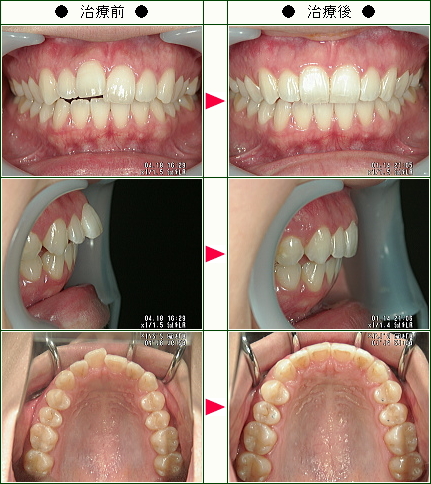

☆歯のデコボコ矯正症例(T・A様 25歳 女性)